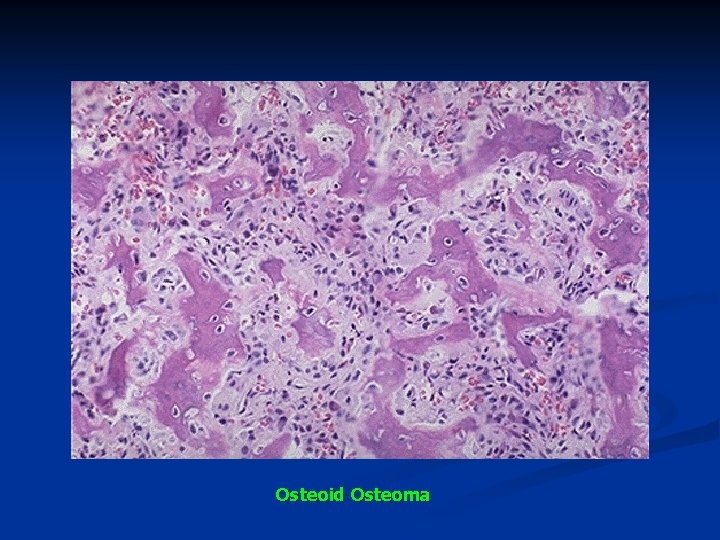

n Microscopy n The nidus: n narrow trabeculae of osteoid or newly formed bone produced by osteoblasts + vascularized stroma n surrounded by a sclerotic mature bone.

Osteoid Osteoma